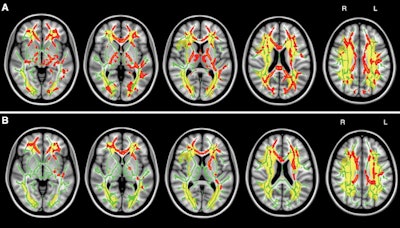

Maps of white-matter tract mean diffusivity and global cognition (A) show where increased mean diffusivity correlates with global cognitive decline (red). Also tracked is total ischemic lesion distribution (yellow) with T1-weighted images (B) to show mean diffusivity and fluency. Image courtesy of Radiology.

More specifically, cognitively impaired patients had larger normalized acute lesion volumes (5.9 ± 11.3), compared with cognitively intact individuals (2.7 ± 5.1), as well as greater chronic subcortical ischemic volumes (15.5 ± 15.5 versus 8.0 ± 10.5). The trend continued with more cortical infarctions in four cognitively impaired patients, compared with no such infarctions among the cognitively intact participants.

Most significantly, chronic subcortical ischemic lesions were found in the anterior thalamic and interhemispheric fiber tracts, as well as severe white-matter tract damage, both of which are associated with cognitive impairment.

"Our research demonstrated subcortical white-matter ischemic lesion locations and severity of microscopic white-matter tract damage contribute to cognitive impairment in symptomatic carotid artery disease," Meng said. This "suggests that subcortical disconnection within large-range cognitive neural networks is a key mechanism of vascular cognitive disorder."